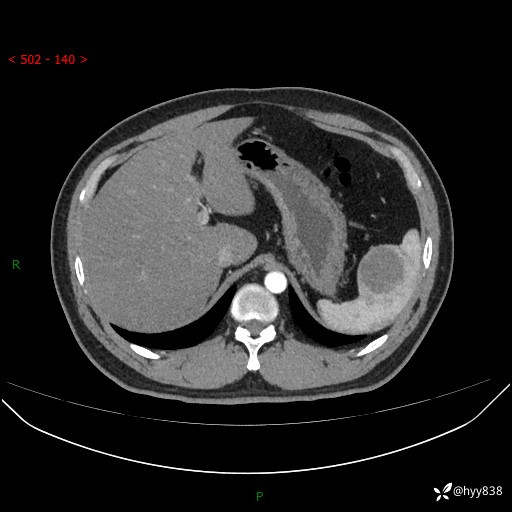

【患者信息】:31岁/男

【主诉】:超声发现脾脏肿物,为进一步诊治来我院,门诊以“脾脏占位”收入院

【检查】:上腹部CT平扫+增强